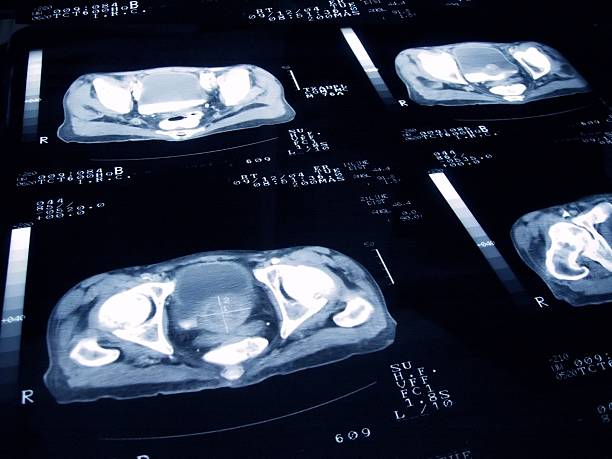

남성 생식기의 요로계와 직접적 연관이 있는 전립선은 사과 모양으로 배꼽 아래쪽에 위치해 있으며 상당히 중요한 역할을 하고 있습니다. 전립선은 사정을 조절하고, 정자의 움직임을 돕는 전립선 분비액을 만들어냅니다. 이 분비액은 정자의 영양 공급과 이동에 필수적인 성분을 포함하고 있습니다. 또한, 전립선은 방광을 둘러싸고 있는 방광 경화근과 골반 바닥 근육에 대한 지지 구조 역할을 할 수 있어 상당히 중요하나 전립선에도 암이 발병될 수 있어 초기에 원활한 대응을 해야만 합니다. 그럼 이번 시간에는 전립선암 초기증상에 대해 자세히 정리해보겠습니다.

전립선은 건강한 남성에서도 점차 커지는 경향이 있습니다. 이것은 일부 남성에서 방광 또는 요도의 진입부를 압박할 정도로 커지기도 하며, 이러한 상황이 발생하면 소변 관련 증상이 발생할 수 있습니다. 전립선의 비대는 나이가 들수록 더 많이 일어날 수 있지만, 전립선 비대가 반드시 전립선암을 유발하지는 않는 것으로 알려져 있습니다.